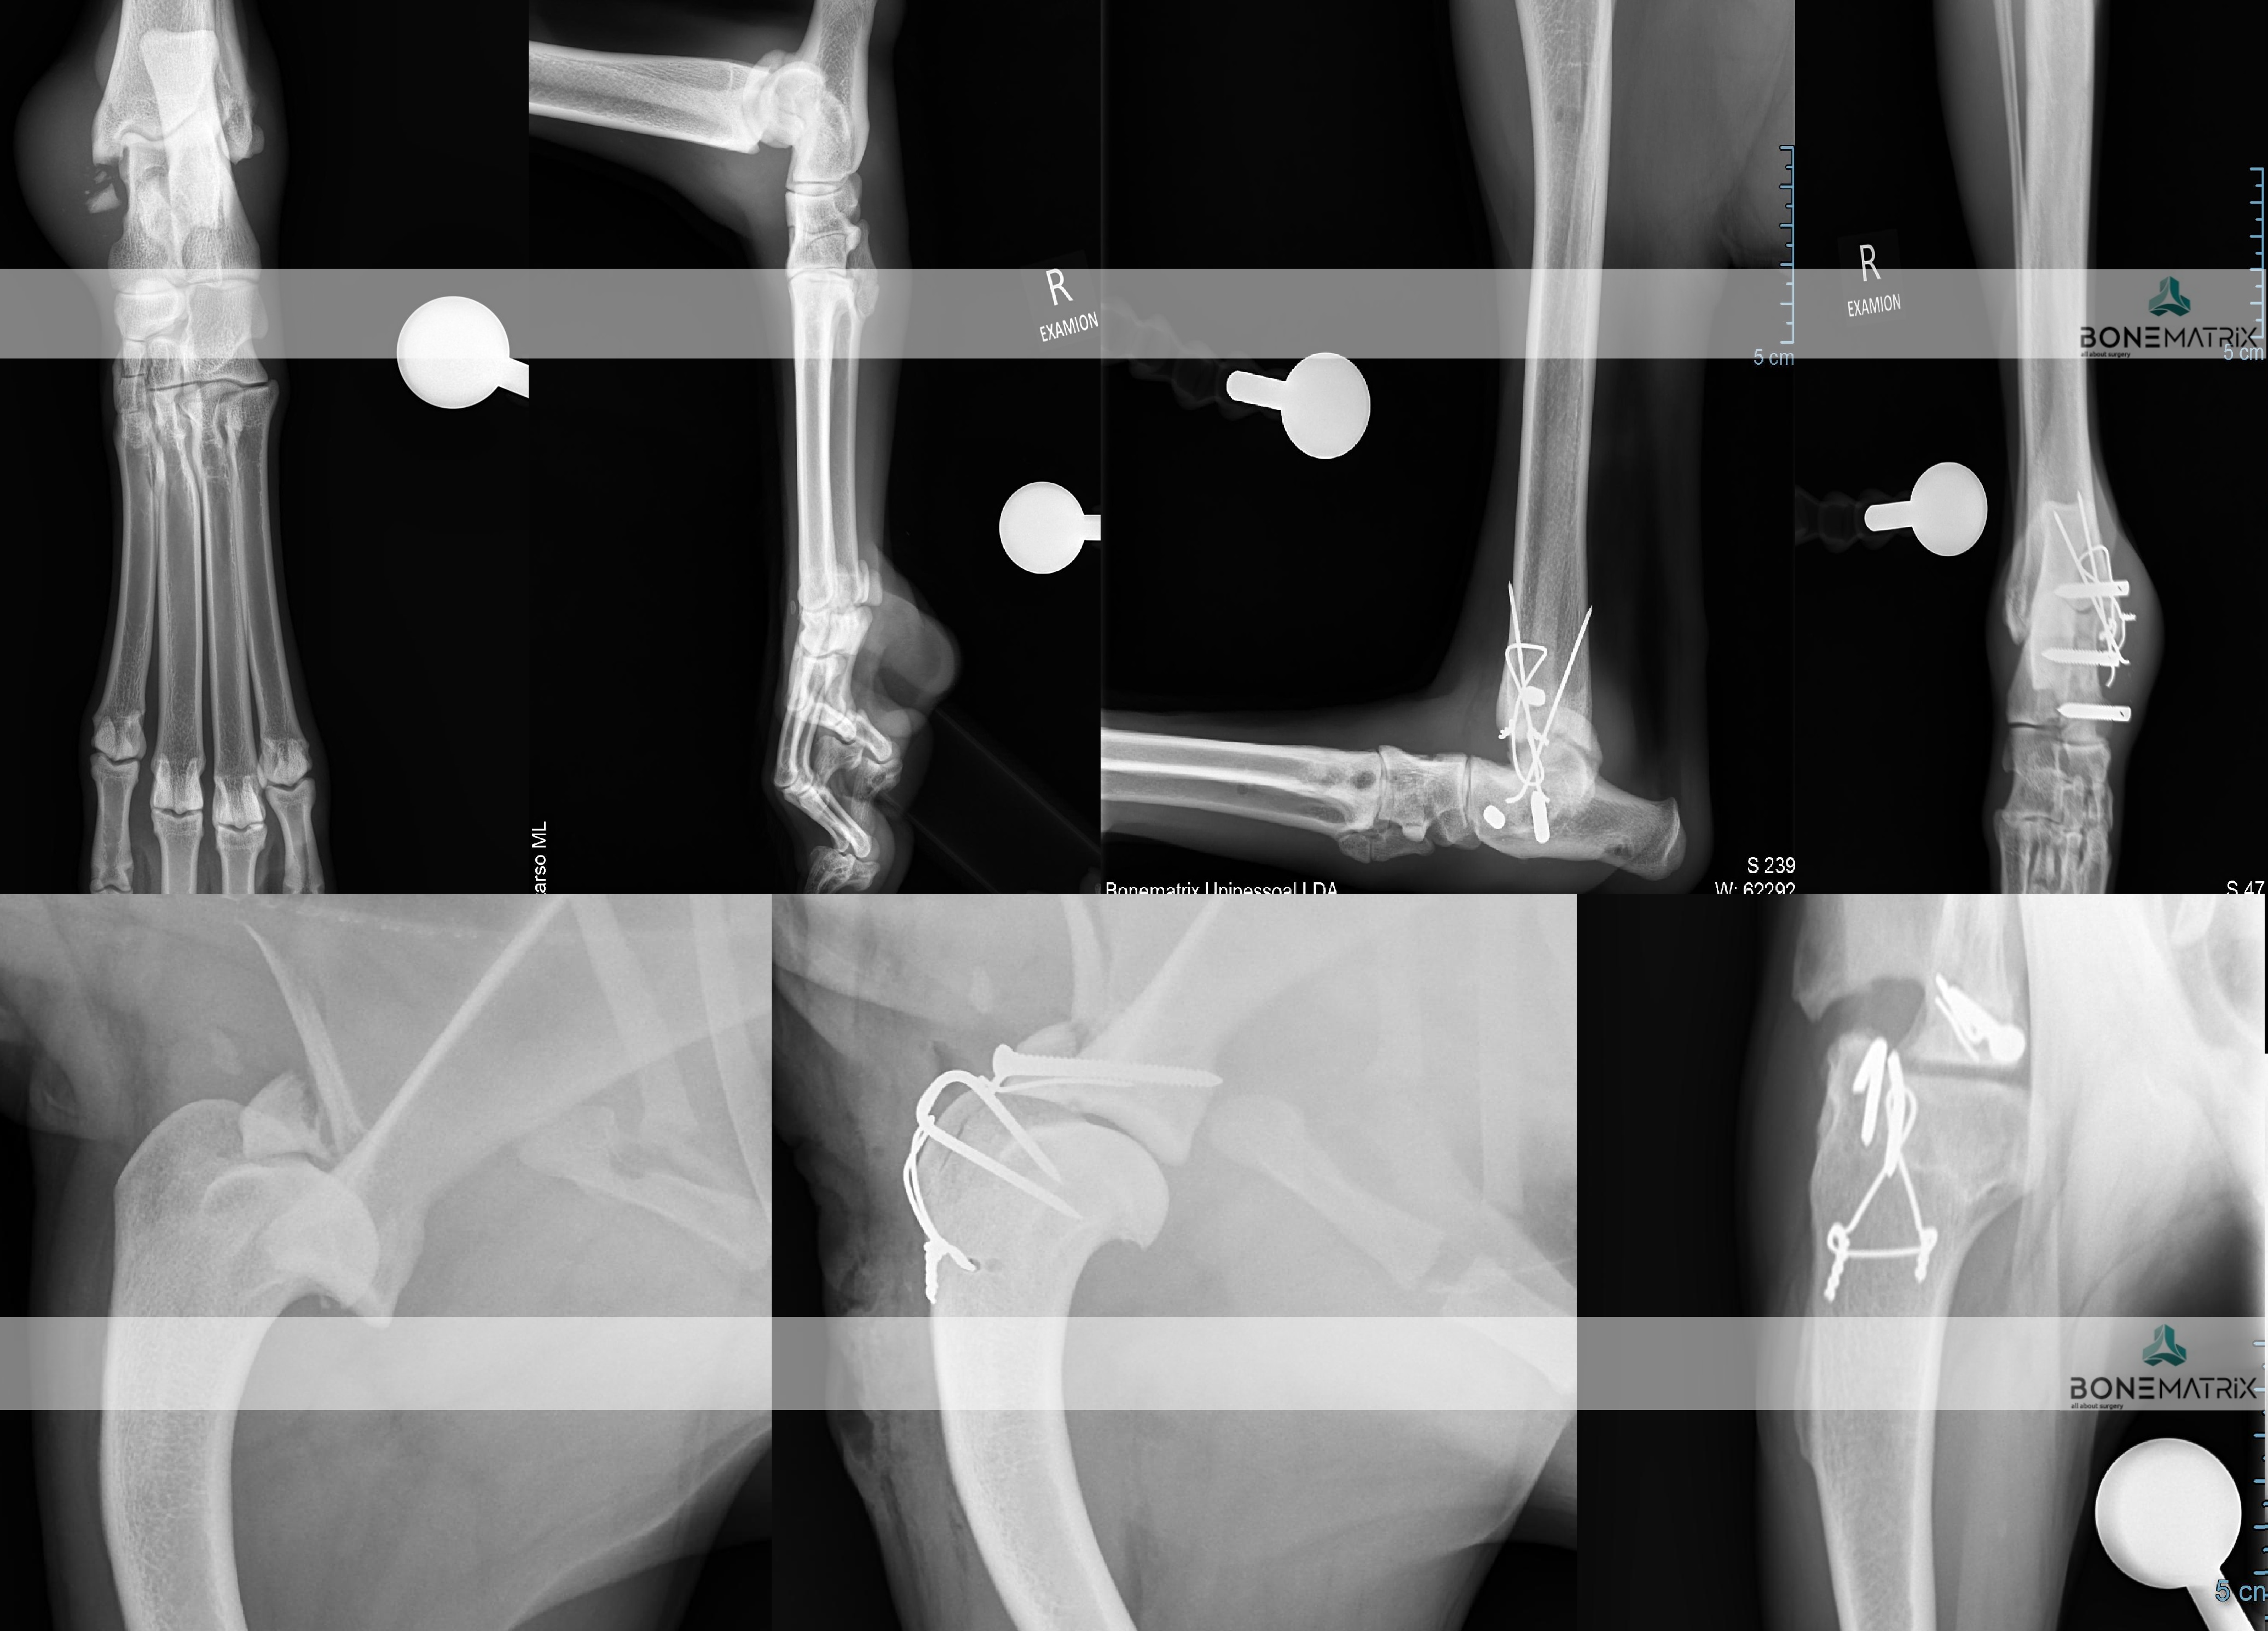

O que é?

As bandas de tensão são um método de estabilização de fraturas utilizado onde existem grandes forças de tensão a atuar, ou seja, onde o movimento dos músculos, vai tender para afastar o fragmento criado.

Esta técnica tem por objetivo transformar esta força de tensão na força contrária contribuindo assim para a estabilização e cicatrização da fratura.

Para a realização desta técnica são utilizados K-wires e cerclage (fio ortopédico).

A complexidade da aplicação desta técnica cirúrgica a maioria das vezes compreende um nível básico de conhecimentos de cirurgia ortopédica e traumatologia. Contudo estes casos podem tornar-se bastante desafiantes conforme o porte do paciente (mais pequeno) ou o tamanho e localização dos fragmentos, sendo nestes casos necessário um nível de formação avançada.

Quando é aplicada esta técnica cirúrgica?

Esta técnica é aplicada em várias situações onde existem forças de tensão importantes a atuar sobre o foco de fratura, destes casos fazem parte:

As fraturas articulares podem ser estabilizadas com recurso aos mais diferentes sistemas de estabilização ou a uma combinação entre estes.

A complexidade das fraturas articulares está associada à capacidade de fazer uma perfeita redução anatómica (devolver a forma normal do osso). Por este motivo estas fraturas constituem frequentemente um trabalho onde é necessário um nível de conhecimento avançado em técnicas cirúrgicas de ortopedia e traumatologia para que se consiga um um bom outcome cirúrgico.